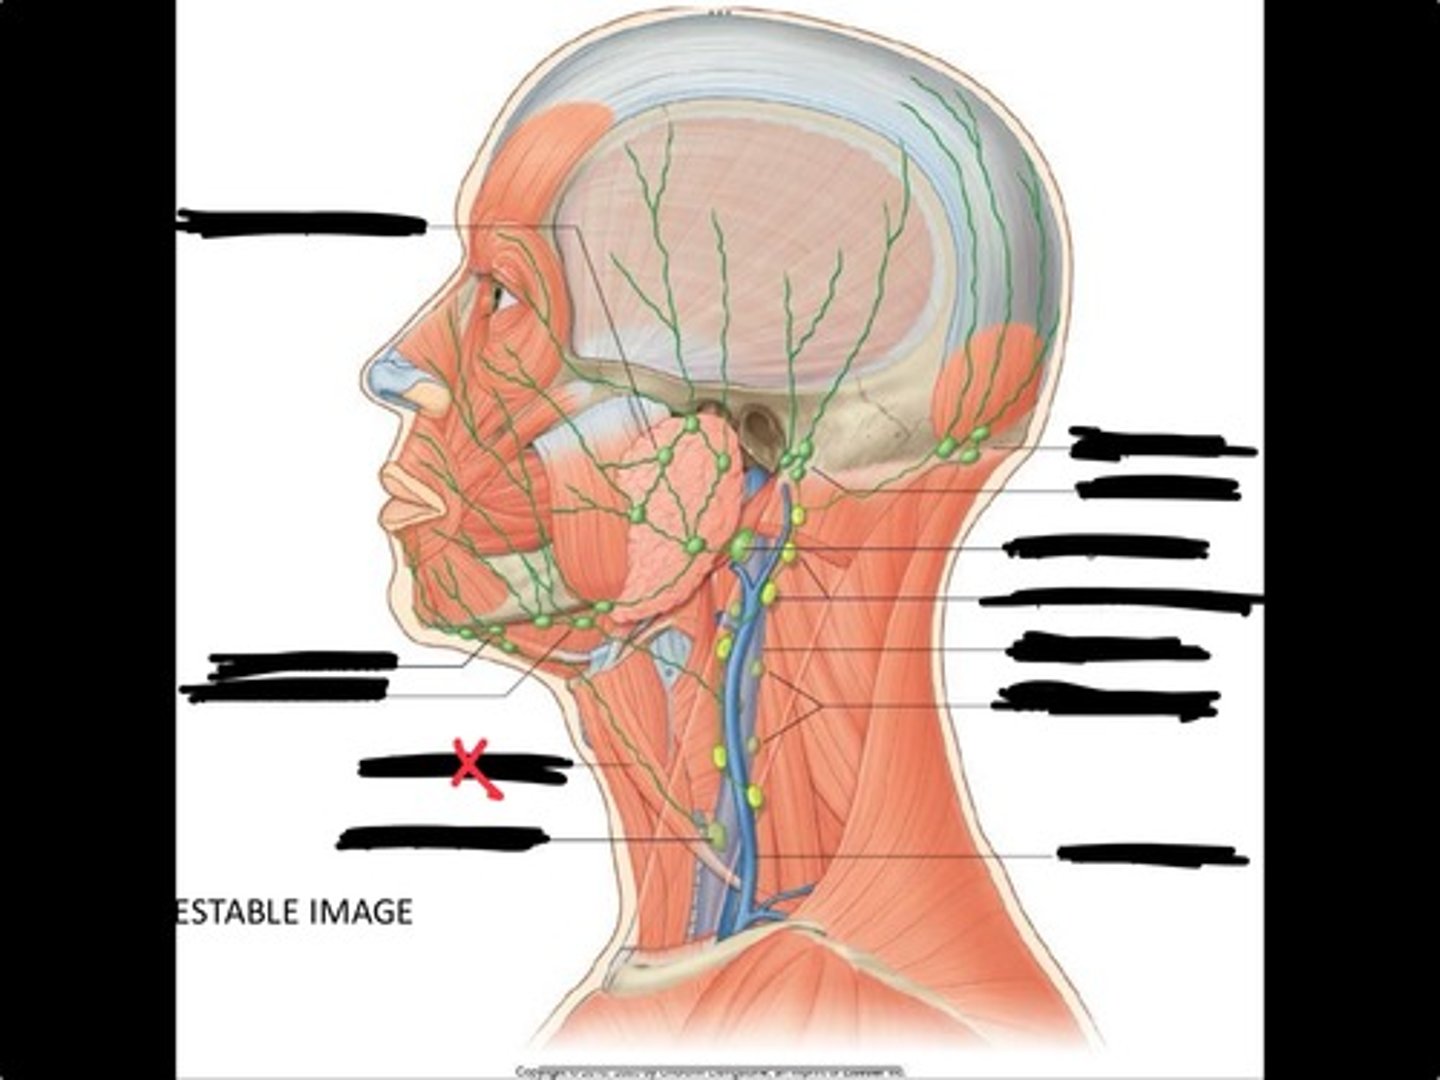

Jugulo-omohyoid node

Omohyoid muscle

Submandibular nodes

Submental nodes

Pre-articular/parotid nodes

Occipital nodes

Mastoid nodes

Jugulodigastric nodes

Superficial cervical nodes

Internal jugular vein

Deep cervical nodes

External jugular vein